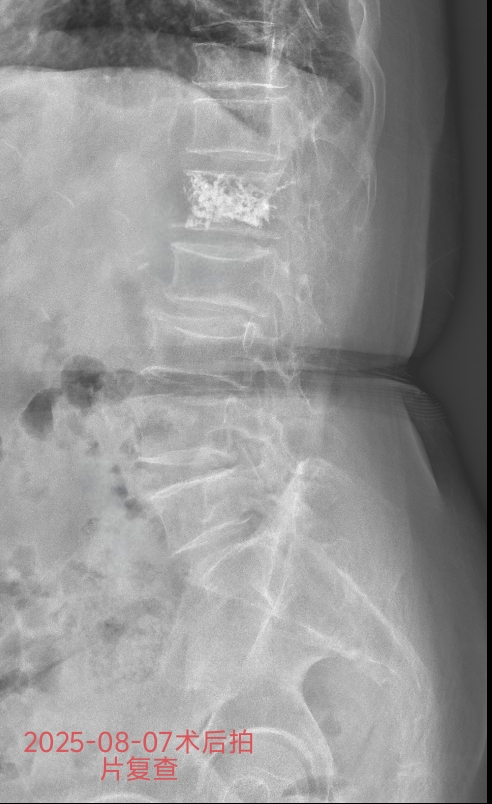

方奶奶入院后,骨科团队全面评估其心肺功能等指标,量身定制PKP手术方案。主治医师王亮在局部麻醉下通过微小切口,在影像精准引导下将穿刺针植入病变椎体,注入骨水泥加固,水泥弥散良好。整个过程耗时不到1小时,创伤小、出血少,术后无需长时间禁食。

术后2小时,李奶奶就能自行翻身及下地短距离行走,腰部疼痛感明显减轻;术后,各项检查指标平稳,顺利出院。

PKP手术通过骨水泥的支撑作用,可快速恢复椎体稳定性、缓解疼痛,帮助患者尽早脱离卧床状态,大幅降低并发症风险。对于老年骨质疏松性椎体骨折患者,及时选择PKP手术,能有效缩短康复周期,减少病痛对生活的影响。